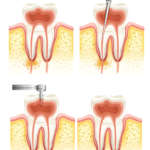

L’importanza di sagomatura e detersione dei canali radicolari Premium

Conoscere con precisione la morfologia dell’elemento dentale per pianificare le fasi del trattamento e scegliere lo strumentario più adatto